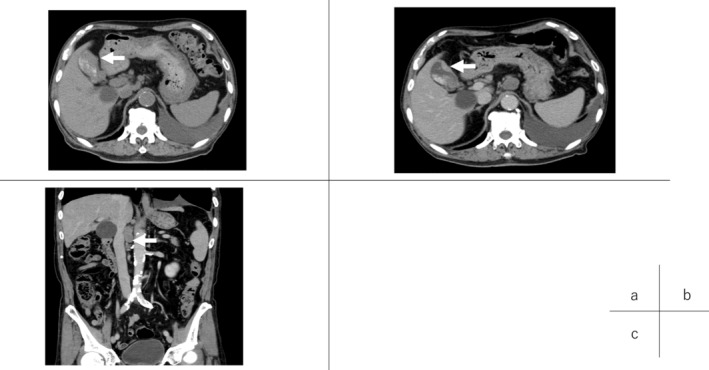

Generally, prognosis of GB carcinoma with lymph node metastasis and SCNEC is quite poor. 14 , 15 The patient, an octogenarian, had performance status of 0 (CTC Version 2.0), but he had various critical comorbid diseases such as recurrent lung cancer. Therefore, we first recommended chemotherapy instead of definitive surgery. However, the standard platinum‐based regimen of SCNEC proved intolerable because of his general status. Although there are few studies suggesting that nivolumab is effective against neuroendocrine carcinoma and GB cancers, 13 , 16 nivolumab monotherapy (240 mg, every 2 weeks) was initiated. At that time, neuron‐specific enolase (NSE) was significant (35.7 ng/mL). After 10 courses of nivolumab, a CT scan showed that the GB tumor had shrunk without remarkable lymphadenopathy in the hepatoduodenal ligament, but with limited lymphadenopathy adjacent to the abdominal aorta (Figure 2). A tumor marker, NSE, turned negative (12.9 ng/mL) (Figure 3). Even though prognosis of GB carcinoma with lymph node metastases is quite poor (median OS: 13.5 months), 17 radical resection of the tumor can prolong survival in cases in which metastases disappear after chemotherapy. Therefore, we decided to operate, for the following reasons: (1) We could remove the tumor completely with lymphadenectomy next to the abdominal aorta. (2) If the tumor had increased during further nivolumab monotherapy, we would have been unable to achieve complete surgical resection.

FIGURE 2.

CT images (A) before chemotherapy and (B, C) after 10 courses of nivolumab. After nivolumab, the tumor had clearly shrunk (B, arrow), but limited lymphadenopathy proximal to the abdominal aorta emerged (c, arrow).